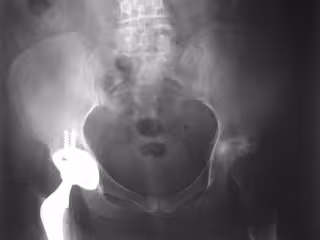

Reemplazo de cadera

La enfermedad de Párkinson, la osteoartritis, las enfermedades reumáticas, el alcoholismo y los trastornos de salud mental aumentan el riesgo de complicaciones quirúrgicas después de una cirugía de fractura de cadera, según ha evidenciado un estudio llevado a cabo por expertos de la Universidad de Finlandia Oriental, el Hospital Universitario Kuopio, la Universidad de Helsinki y el Instituto Nacional de Salud y Bienestar de Finlandia.

Los datos incluyeron 68.800 pacientes con fractura de cadera, es decir, todos los pacientes mayores de 50 años que tuvieron su primera fractura de cadera en Finlandia en 1999-2011. Así, los investigadores comprobaron que el tratamiento de la fractura de cadera se asociaba a un riesgo significativo de complicaciones quirúrgicas.

En concreto, el 4,6 por ciento de los pacientes experimentaron complicaciones quirúrgicas dentro de los tres meses posteriores a la cirugía, hecho que, según los expertos, se explica porque la elevada edad de los pacientes y sus comorbilidades. Además, el riesgo de complicaciones quirúrgicas fue más elevado en pacientes con osteoartritis, enfermedad de Párkinson, enfermedad reumática, dependencia del alcohol, depresión o trastorno psicótico.

Finalmente, la cirugía de reemplazo total de cadera se asoció con más complicaciones quirúrgicas que otros métodos de tratamiento, y el 10 por ciento de los pacientes con cirugía de reemplazo total de cadera experimentaron una complicación.